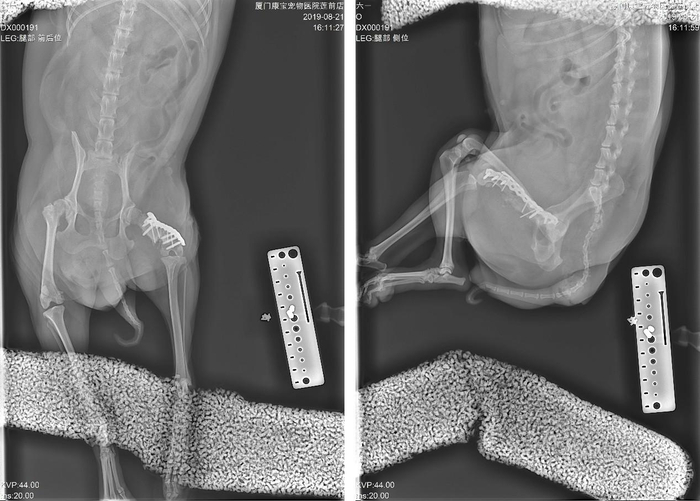

因考虑到恢复期长,才有外侧及前侧双板固定的方式,并从同侧肱骨及髂骨翼移植大量骨松质在骨折断端,最大程度的促进骨骼愈合。

病情预后:

后期的恢复还算顺利,伤口一期愈合,术后一周就开始用患肢点地了,之后每月复查。6个月后,可以观察到骨折断端基本愈合,能用患肢正常走路。